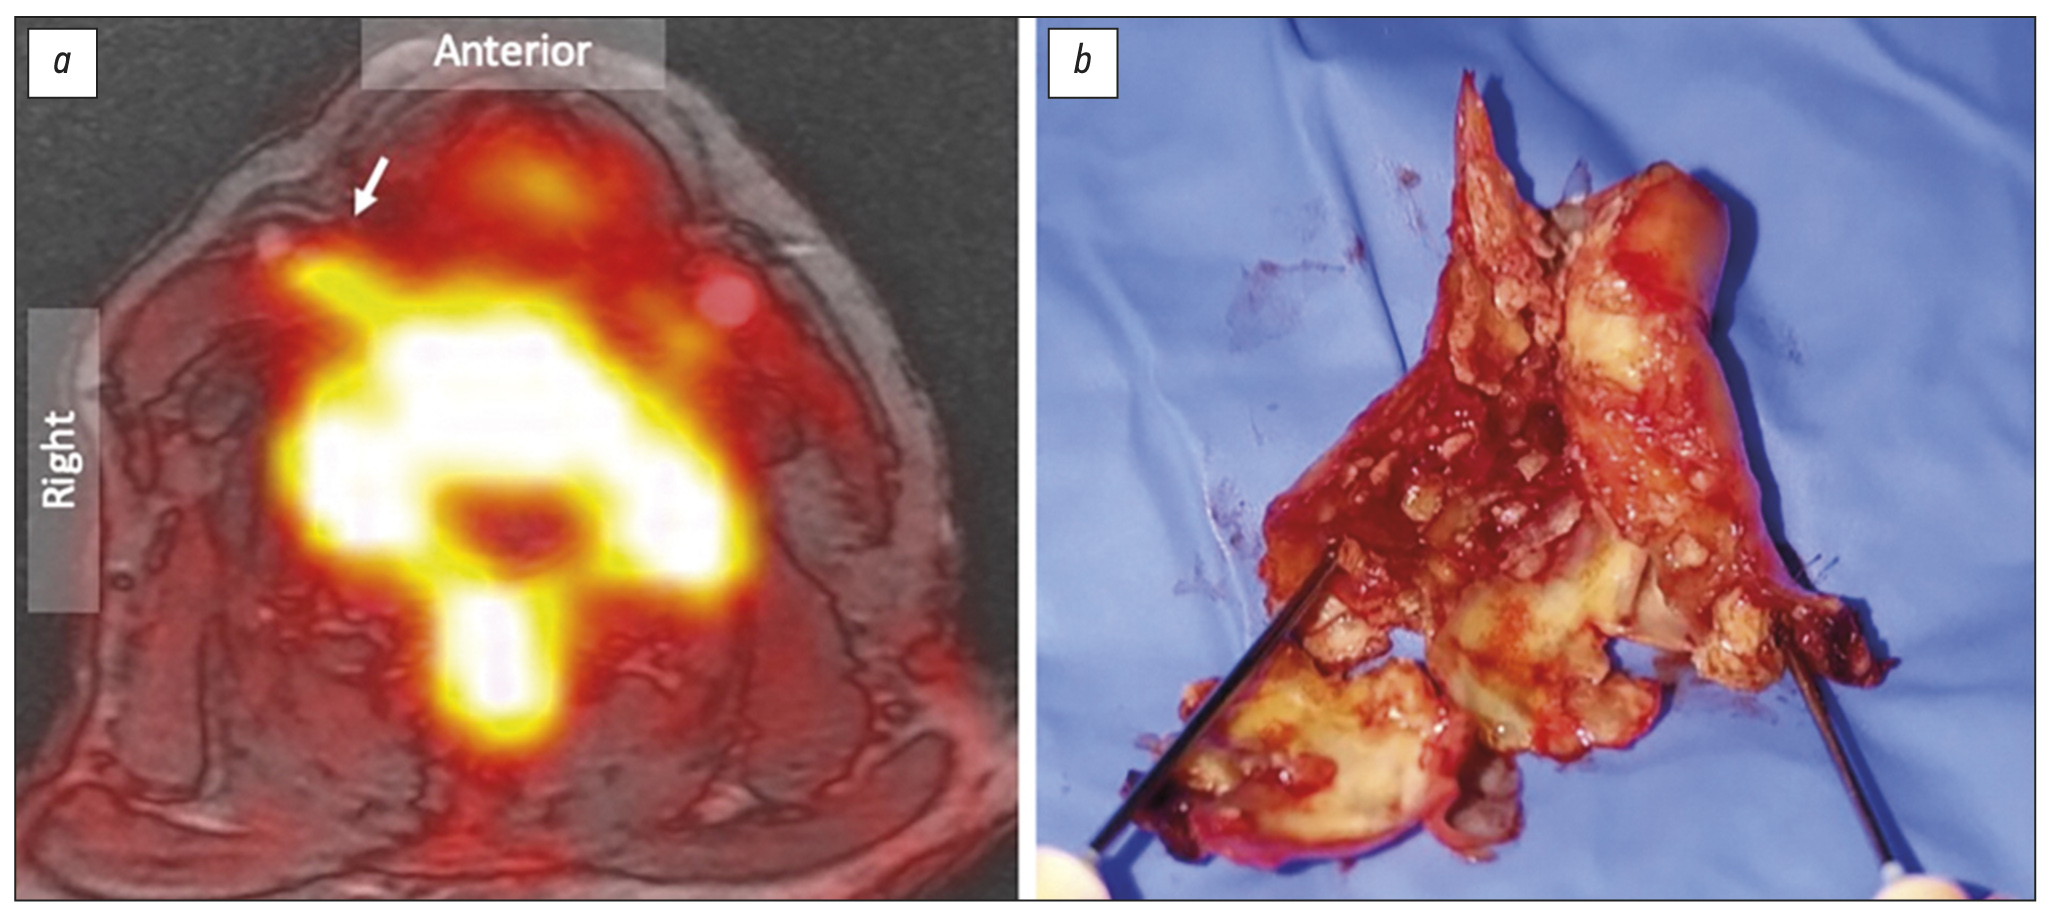

Additional imaging techniques, such as contrast-enhanced ultrasound, and multiparametric or USPIO-enhanced MRI, can identify unstable and culprit atherosclerotic plaque. Moreover, PET imaging with 18F-FDG or 18F-NaF PET can detect the biological activity of culprit plaques, with 18F-NaF in particular binding to culprit carotid lesions characterized by a lipid-rich necrotic core (Figure 4).69 The combination of PET/MRI offers a substantial improvement with the potential to assess simultaneously for flow, thrombus, lipid core, plaque rupture and necrotic unstable plaque with microcalcification.

Fig. 4. 18F-sodium fluoride positron emission tomography and magnetic resonance angiography of symptomatic lesion of the right internal carotid artery.

(A) Combined 18F-Sodium fluoride positron emission tomography superimposed on MR angiogram localizes focal radiotracer uptake in the culprit right internal carotid artery plaque (arrow). (B) Surgical endarterectomy confirms a highly ulcerated lesion with positive remodelling and marked intimal irregularity